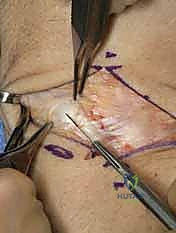

1. Incision and Initial Dissection

Our first step is to gain access to the dorsal wrist capsule.

- Skin Incision: I'm making a longitudinal skin incision approximately 4-5 cm in length, centered directly over the third extensor compartment. This compartment houses the extensor pollicis longus (EPL) tendon. The incision should be roughly centered over Lister's tubercle, which you can palpate as a bony prominence on the dorsal aspect of the distal radius.

TECH FIG 1 • A. Axial image of dorsal wrist compartments with arrow indicating location for skin incision over third compartment. B. Skin incision centered over third dorsal compartment with superficial branch of the radial nerve (SBRN) and dorsal sensory branch of the ulnar nerve (DSBUN). Oval indicates tubercle of Lister. (Copyright © Mayo Clinic.)

> **Surgical Warning:** As you make your skin incision, be acutely aware of the **dorsal sensory branch of the ulnar nerve (DSBUN)**. This nerve runs subcutaneously along the ulnar side of the wrist and is highly vulnerable. Use careful, sharp dissection, identifying and protecting it with fine vessel loops or retractors. Similarly, the superficial branch of the radial nerve (SBRN) is on the radial side, though less likely to be in our direct field here.

- Subcutaneous Dissection: We'll carefully dissect through the subcutaneous tissue, identifying and ligating any superficial veins to maintain a clear field.

- Extensor Retinaculum Division: Now, we'll identify the extensor retinaculum. I'm dividing the retinaculum directly over the third extensor compartment, releasing the extensor pollicis longus (EPL) tendon. This allows us to mobilize the EPL radially, providing better access to the underlying capsule.